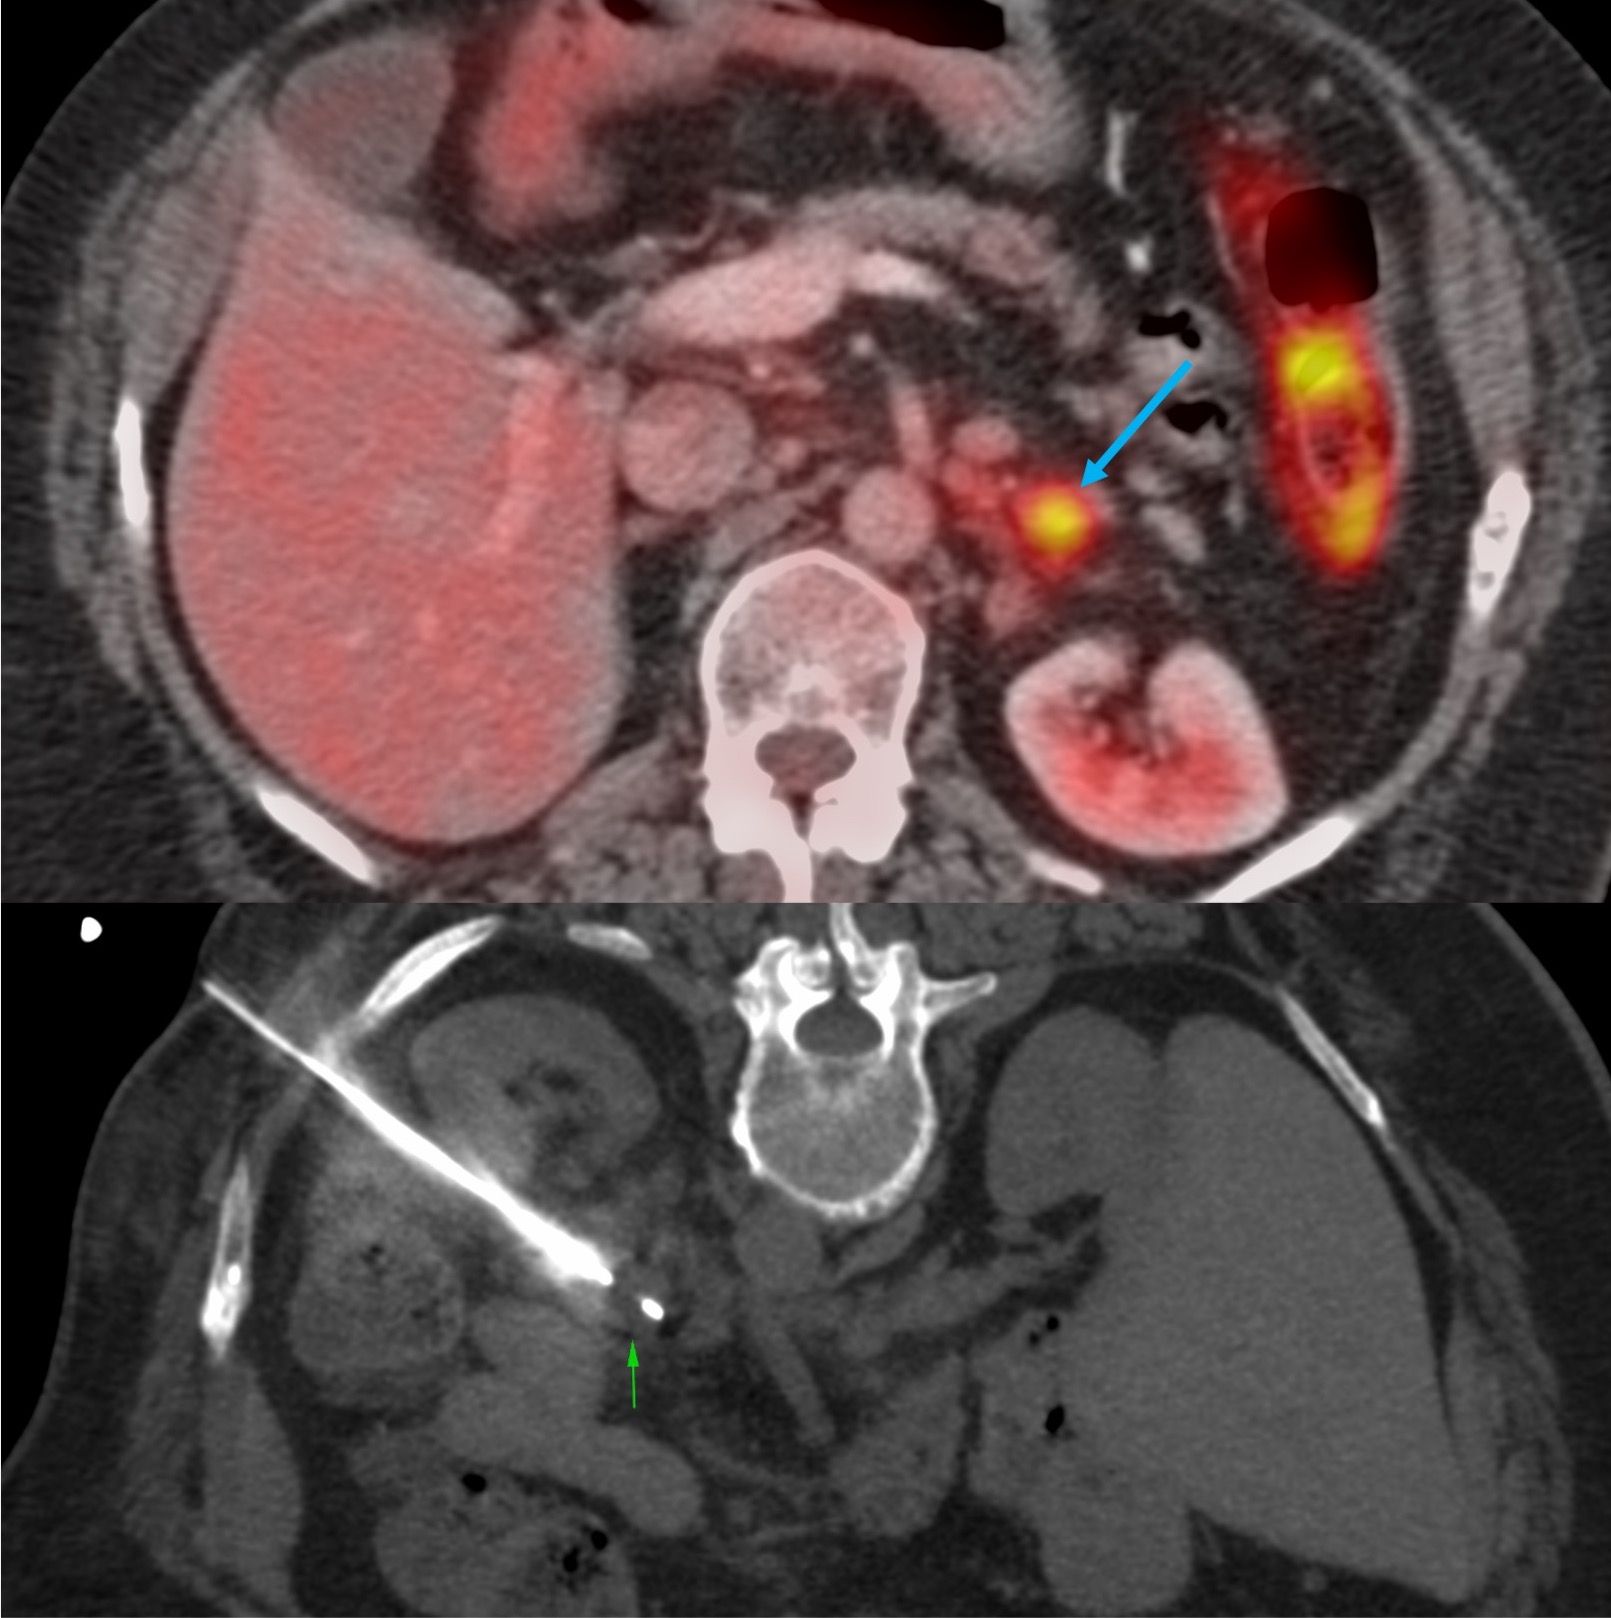

Case 22: 70-Years Lady with a Left Adrenal Nodule - Prone Posterolateral Approach

Case 20: 2.1 cm Renal Mass Biopsy